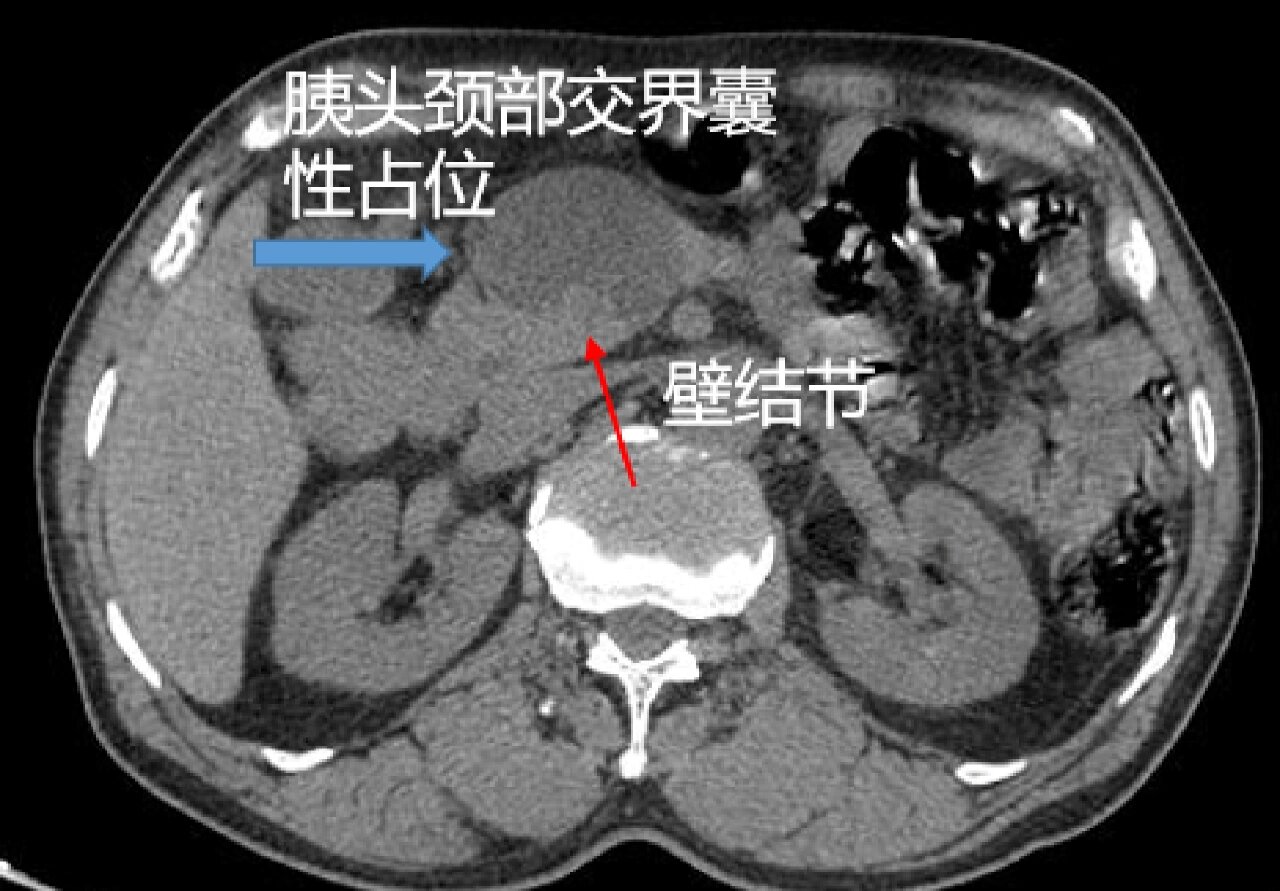

胰腺囊腺瘤是什么样子的?如何判断良恶性?该不该手术?